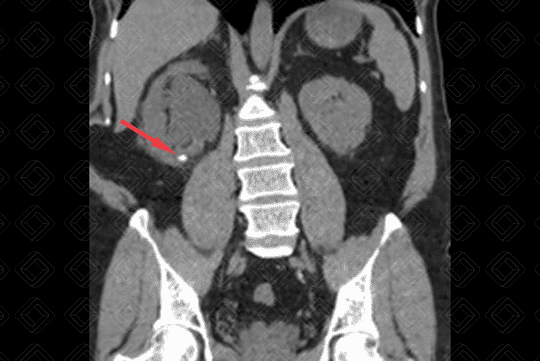

Texto alternativo para a imagem Figuras 1 e 2. Créditos: Dra Elazir Mota - Rio de Janeiro/RJ

Descrição das figuras 1 e 2: Tomografia computadorizada do abdome sem a administração do contraste venoso evidencia cálculo no terço inferior do rim direito (seta vermelha), medindo 0,6 cm e com densidade de 780 UH (figura 1).

• Tomografia computadorizada do abdome: Exame padrão-ouro. Na tomografia computadorizada do abdome é sempre importante descrever a quantidade de cálculos, suas dimensões, densidade (por meio da densidade, podemos saber a respeito da composição do cálculo) e localização. Importante lembrar também que para avaliação de litíase, seja ela renal, ureteral ou vesical, o estudo deve ser feito sem a administração do contraste venoso. A administração de contraste fica reservada para avaliação de complicações, como suspeita de pielonefrite ou abcessos renais. Vale destacar que o cálculo de Indinavir (inibidor de protease - medicação para HIV) também não é visualizado na tomografia.